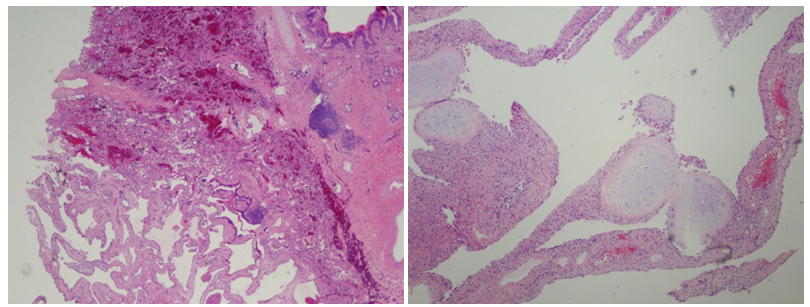

A previously healthy 5 year old female admitted to the Miller Children’s Hospital for right-sided pneumonia was found to have chest radiography (CXR) concerning for right-sided congenital emphysematous lung lesion [1-3]. Her presenting symptoms included shortness of breath with activity limitation and dyspnea with associated generalized abdominal pain. Her only significant past medical history included tonsilloadenoidectomy for obstructive sleep apnea. Her parents also reported a single emergency room visit at one year of age for wheezing, although she was not formally diagnosed with asthma or on controller therapy. She was initially treated with antimicrobials and pediatric pulmonology was consulted regarding her abnormal CXR (Figure 1-7).

Figure 1 CXR at presentation.

Physical examination was notable for tachypnea with a maximal respiratory rate of 48 breaths per minute, tachycardia, pulse oximetry (SpO2) of 92%, diminished air exchange at right chest with asymmetric barrel chest (right > left) including increased anteroposterior diameter. Flexible fiberoptic bronchoscopy with bronchoalveolar lavage (FFB BAL) demonstrated mucoid impaction of the right mainstem bronchus causing ball-valve mechanism leading to air trapping with herniation of the right lung to the left. There was mucoid impaction within the right upper lobe (RUL) and right middle lobe (RML) bronchi, tracheobronchomalacia, particularly with the posterior distal trachea, and bronchomalacia of the right middle lobe bronchus and RUL bronchus. The mucosa of the tracheobronchial tree had diffuse inflammation. Airway clearance including beta-2 agonist were added to her inpatient treatment regimen, and further imaging obtained including chest CT with angiography (CTA) and ventilation-perfusion (V/Q) scan. The CTA revealed severe hyper expansion of the RML with multiple cysts that occupied the majority of her right hemithorax. The hyper expanded lobe was compressing atelectatic but otherwise normal appearing RUL and right lower lobe (RLL) parenchyma with severe mediastinal shift to the left. Lung V/Q scan showed minimal contribution by the right lung of only 11.3% with limited-to-no perfusion.